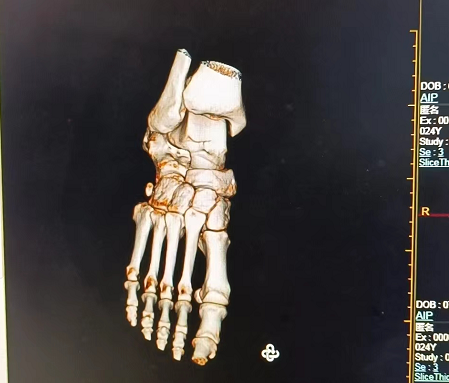

啟動項更改后正常進入系統(tǒng),進入系統(tǒng)后做病人掃描,然后進行三維重建,圖像如下

后做三維重建圖像正常,故障排除。后做系統(tǒng)BACKUP和C盤鏡像